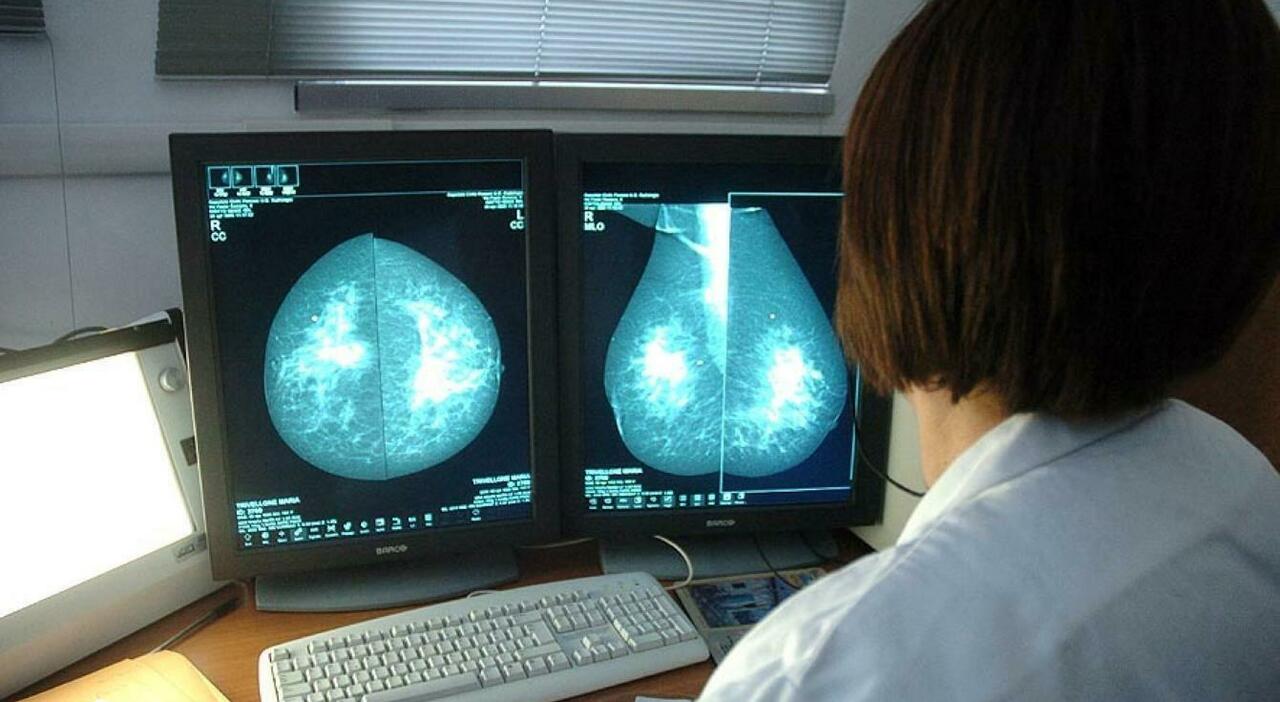

La Campagna Ottobre Rosa è un’iniziativa promossa dalla Regione Lazio, che offre alle donne di età compresa tra i 45 e i 49 anni l’opportunità di prenotare una mammografia gratuita. Questo programma si rivolge a quelle donne che non rientrano nella fascia garantita dal programma di screening, fornendo loro la possibilità di sottoporsi a controlli preventivi. Le mammografie possono essere prenotate presso le strutture sanitarie partecipanti all’iniziativa fino ad esaurimento della disponibilità.

Le mammografie sono uno strumento essenziale nella diagnosi precoce del tumore al seno, in quanto permettono di individuare eventuali formazioni tumorali anche in fase iniziale. Le donne di età compresa tra i 45 e i 49 anni che non rientrano nel programma di screening possono sfruttare l’opportunità offerta dalla Campagna Ottobre Rosa per sottoporsi a controlli gratuiti e tutelare la propria salute.